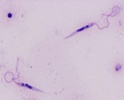

Scientific Name | Leishmania major |

Comments | from Promastigote (culture form) |

Specimen Condition | Live Specimen |

© 2008 Jan Votępka